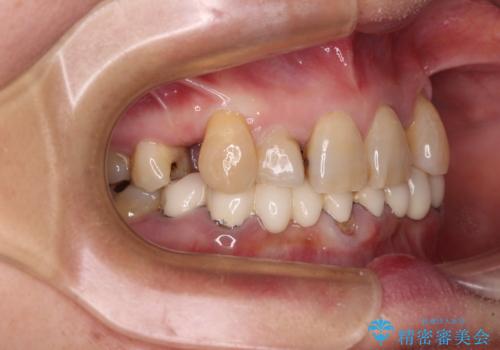

- 常に外れている下顎のブリッジと、前歯のデコボコと色を気にして来院された患者様です。

前歯のデコボコおよび奥歯の咬み合わせを改善するために、上顎左右の小臼歯を欠損スペースを利用して歯列を整え、矯正治療後に気になる上下前歯などをオールセラミッククラウンで美しく仕上げていくこととしました。